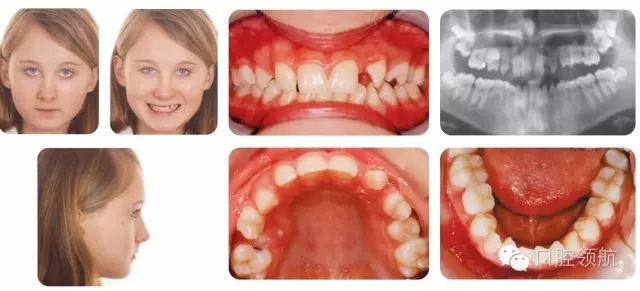

12歲的女性患者,為II類2分類錯牙合,中度骨性II類,后縮側(cè)貌,下頜發(fā)育不足(圖2.23)。

圖2.23

臨床牙列情況

哪顆牙缺失?

X線片檢查顯示UL3和LR5先天缺失,LRE滯留,預(yù)后較好。

該病例的主要問題是什么?

● Ⅱ類切牙關(guān)系。

● UR5和下切牙擁擠。

● 上頜第一前磨牙扭轉(zhuǎn)。

● 上頜后牙段間隙。

● UL3和LR5先天缺失。

● LRE滯留(預(yù)后較好)。